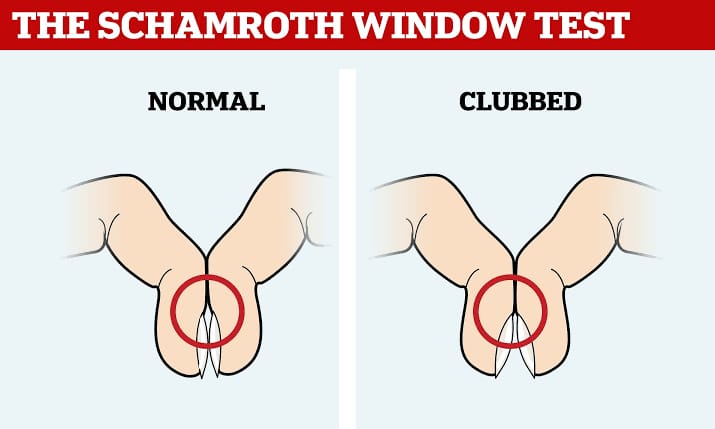

- ફિંગરમાં ક્લબિંગ પ્રેઝન્ટ છે કે નહીં તે ચેક કરવા માટે સ્કાર્મરોથ વિન્ડો ટેસ્ટ કરવામાં આવે છે.

Scharmroth window test (સ્કાર્મરોથ વિન્ડો ટેસ્ટ):

- સ્કાર્મરોથ વિન્ડો ટેસ્ટ એ ફિંગર માં ક્લબિંગ પ્રેઝન્ટ છે કે નહીં તે કન્ફર્મ કરવા માટે વપરાય છે.

- સ્કાર્મરોથ વિન્ડો ટેસ્ટમાં પિક્ચરમાં દર્શાવ્યા મુજબ બંને હાથની એક એક આંગળીના નેઇલ બેડને સાથે રાખવામાં આવે છે અને નેઇલ બેડની વચ્ચે ડાયમંડ શેપ જોવા મળે છે કે નહીં તે ચેક કરવામાં આવે છે.

- જો નેઇલ બેડની વચ્ચે ડાયમંડ શેપ જોવા મળે તો તે નોર્મલ છે જ્યારે નેઇલબેડની વચ્ચે સ્પેસ જોવા ન મળે તો તે ક્લબિંગ ઇન્ડિકેટ કરે છે.